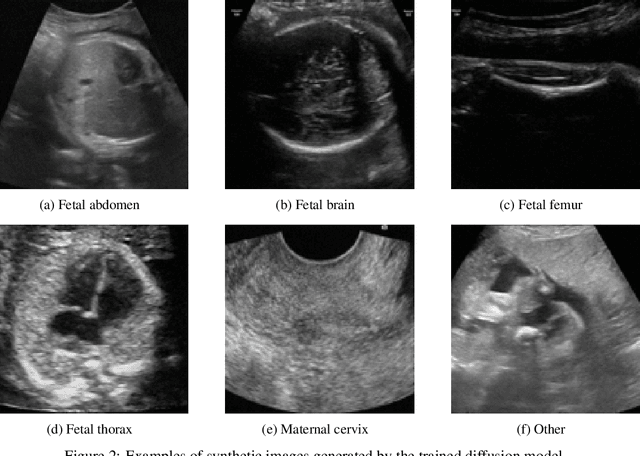

Abstract:Ultrasound imaging is widely used in medical diagnosis, especially for fetal health assessment. However, the availability of high-quality annotated ultrasound images is limited, which restricts the training of machine learning models. In this paper, we investigate the use of diffusion models to generate synthetic ultrasound images to improve the performance on fetal plane classification. We train different classifiers first on synthetic images and then fine-tune them with real images. Extensive experimental results demonstrate that incorporating generated images into training pipelines leads to better classification accuracy than training with real images alone. The findings suggest that generating synthetic data using diffusion models can be a valuable tool in overcoming the challenges of data scarcity in ultrasound medical imaging.